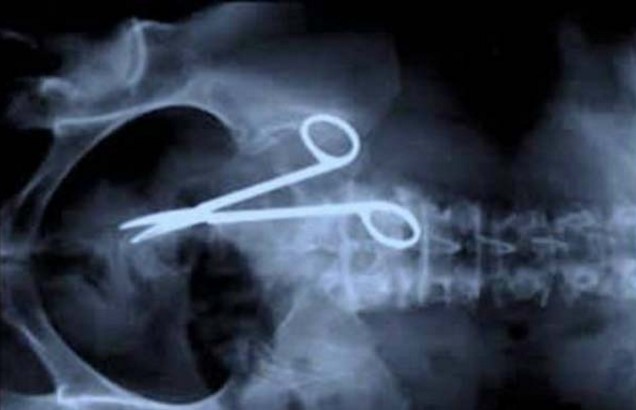

8. Gunting.

9. Gunting lagi.

12. Gunting rambut atau operasi.